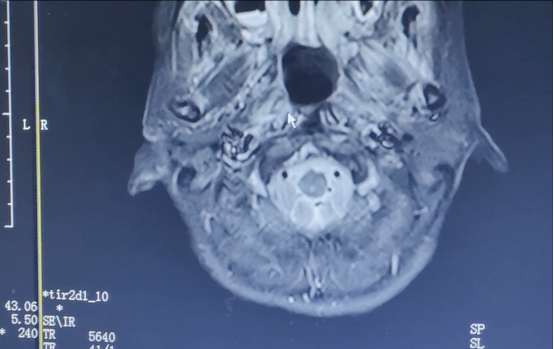

▲2023年7月影像結(jié)果

目前,阿芳的患者病情控制良好,多次復(fù)查均未發(fā)生復(fù)發(fā)或轉(zhuǎn)移,且沒(méi)有發(fā)生影響生活質(zhì)量的放化療相關(guān)不良反應(yīng)?!斑€好當(dāng)時(shí)沒(méi)有放棄?!爆F(xiàn)在的阿芳堅(jiān)持定期復(fù)查,心態(tài)也變好了。